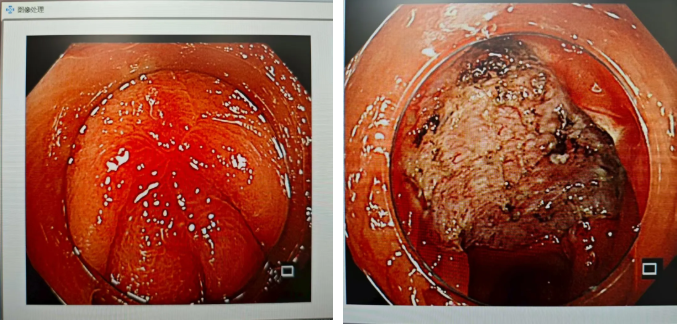

胃竇大彎側一隆起病灶,病理重度異型增生,ESD完整剝離

胃竇大彎側的隆起病灶,同樣屬于重度異型增生,術中精細操作,實現(xiàn)病灶完整剝離,最大程度保護胃壁結構;